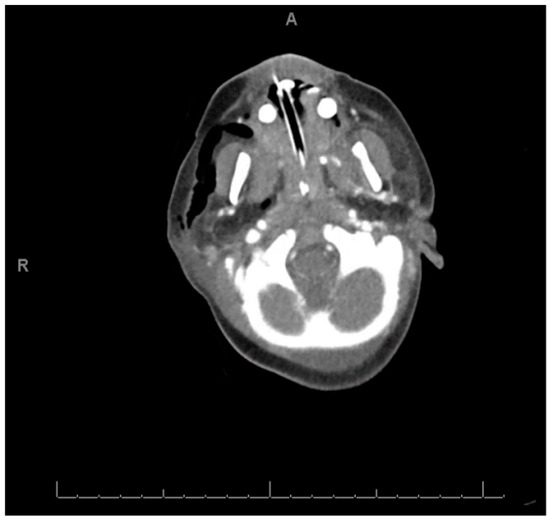

2. Case Report